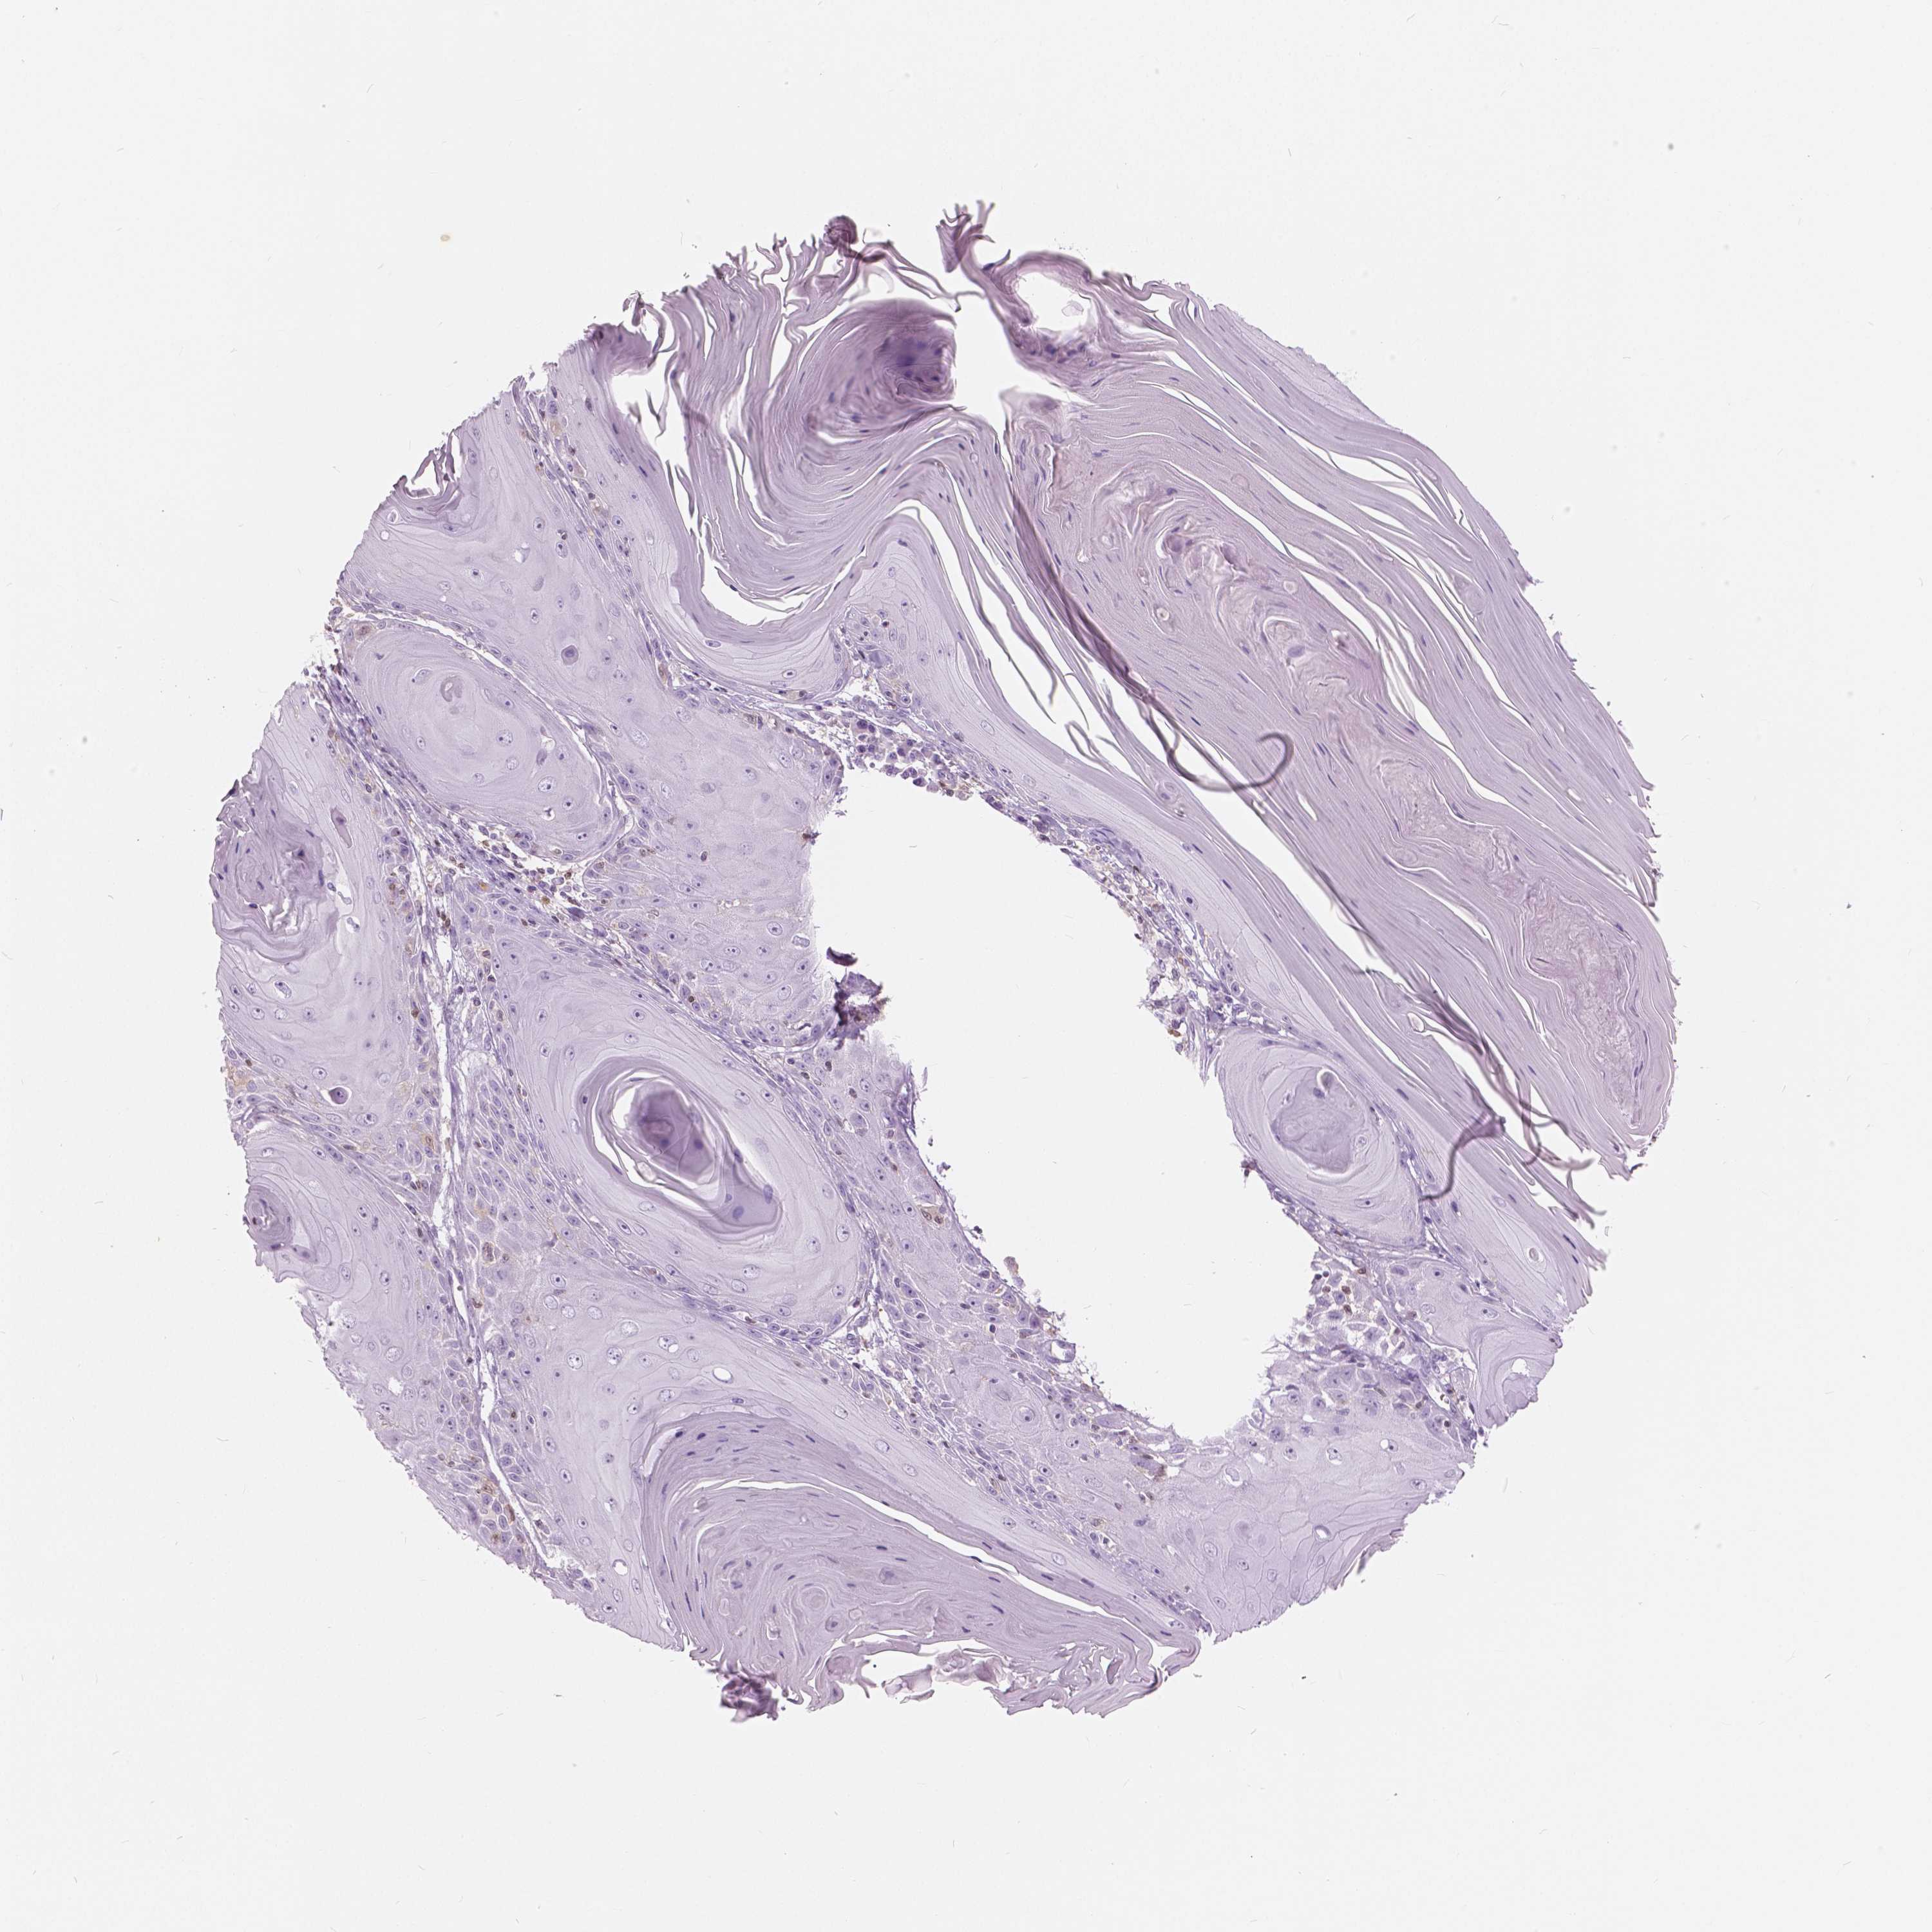

SKIN CANCER - Protein expressioni

A mouse-over function shows sample information and annotation data. Click on an image to view it in a full screen mode. Samples can be filtered based on level of antibody staining by selecting one or several of the following categories: high, medium, low and not detected. The assay and annotation is described here.

Antibody staining in the annotated cell types in the current human tissue is reported as not detected, low, medium, or high, based on conventional immunohistochemistry profiling in selected tissues. This score is based on the combination of the staining intensity and fraction of stained cells.

Each image is clickable and will lead to virtual microscopy that enables deeper exploration of all samples and also displays staining intensity scores, fraction scores and subcellular localization as well as patient and tissue information for each sample.

Basal cell carcinoma

Squamous cell carcinoma, NOS